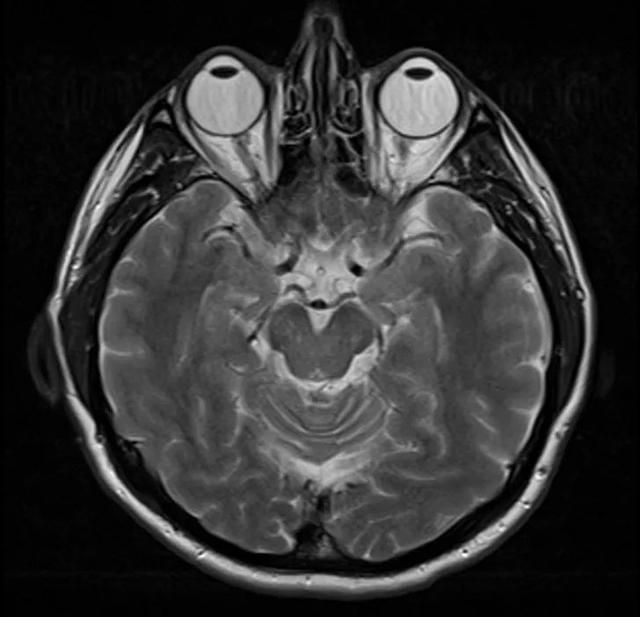

人脑MRI图像,有点可爱??

![]() |